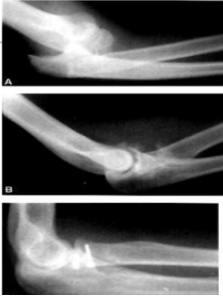

Tipo de fractura en esta rx

Fractura Monteggia anterior (tipo 1)

Mecanismo de lesion de esta fractura

Caída sobre mano extendida con antebrazo en pronación

Fractura de Monteggia posterior (tipo 2)

Trauma directo o lesión de alta energía del antebrazo

CARGA AXIAL CON CODO FLEXIONADO

Tipo de fractura

Fractura de Monteggia tipo 3 (lateral)

Trauma directo al antebrazo o codo, abduccion forzada